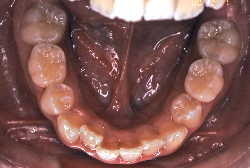

初診時の状態ですが、前歯の噛み合わせが逆転していて、下の前歯が外側に来て、上の前歯が裏側になっています。口元の様子ですが、前歯の重なり方が逆なので、唇の様子もそれを反映して、下唇が突出しています。反対咬合としてはかなり重症です。

分析してみると歯の傾き方に問題があるだけでなく、顎の骨の大きさと形にも問題があることが分かりました。ただし、骨の問題点が見つかったからと言って、必ずしも外科矯正になるわけではなく、このくらいの症状ですと、通常の矯正でもきれいに治すことができます。

診断の結果、下の前歯を正しい位置まで内側に入れていくためには、十分な隙間を確保することが避けられないと判断し、上の左右第二小臼歯と下の左右第一小臼歯は抜歯させて頂くことにしました。歯の本数は減りましたが、歯科医学的評価も大きく改善しましたし、審美的にも大幅な改善が見られますね。特に口元の様子が全然変わりました。